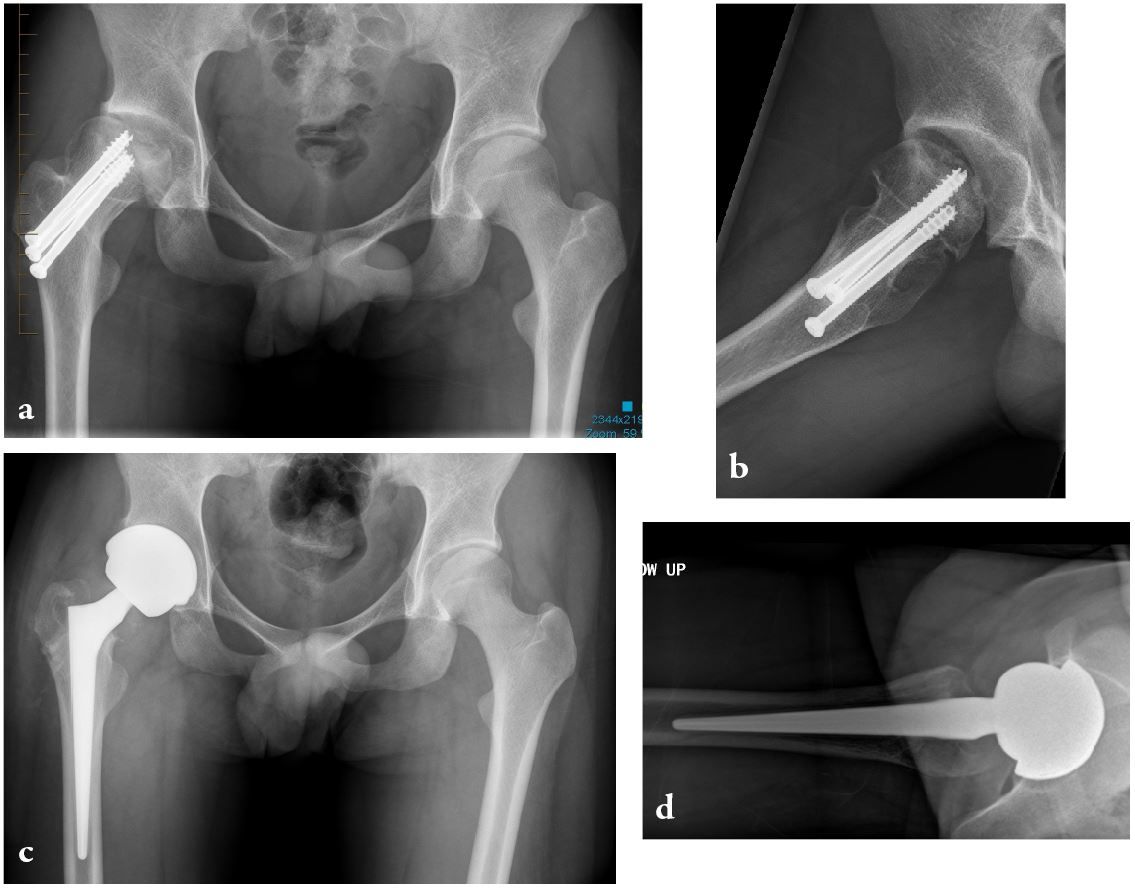

The clinical articles in this issue address several dimensions of hip arthroplasty practice. Topics include revision total hip arthroplasty using cementless stems with bioactive coatings, lessons from 34 years of hydroxyapatite clinical experience, and the rationale for calcar-guided short stems. Further contributions examine total hip arthroplasty in patients with low bone mass and the role of personalized hip joint replacements using large diameter heads in optimizing anatomical restoration and long-term implant performance.